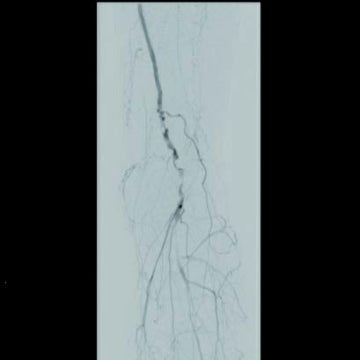

[治療] 右総大腿動脈(common femoral artery:CFA)を逆行性にエコーガイド下に穿刺。山越えで左 CFAまで6 Frガイディングシースを進めた。造影で左SFA起始部付近からベアステント遠位端のやや中枢側まで、TOSAKA分類3のISO病変があることを確認した。ところどころ病変が硬く、0.014 inchガイドワイヤーの先端2.8 gと先端12 gを順次使用して閉塞部位を突破した。PTAバルーン4 mm × 250 mmで前拡張したのち、病変部をカバーするように左SFA末梢側から左SFA起始部にかけてバイアバーン® ステントグラフト6 mm × 250 mmと6 mm × 100 mmを留置し、閉塞したベアステントをフルカバーした。バルーン5 mm × 220 mmで後拡張を実施、血管内超音波(IVUS)と造影で病変部の良好な拡張、血流を確認し手技を終了した(図3)。足関節上腕血圧比(ABI)は0.68から0.92に改善した。さらに6年が経過し、間欠性跛行の再燃があり、ステントグラフトは開存していたが(図4-1)、さらに末梢の膝窩動脈での石灰化プラークによる閉塞病変(図4-2)が原因と考えられた。アテレクトミーデバイスとDCBで膝窩動脈病変を治療して症状は消失した。run offが不良であったにもかかわらず、中枢側のステントグラフトが6年間開存していたことは特筆すべきことである。同患者については現在まで15年にわたり経過をみているが、経年的に動脈硬化が進んでおり、通常のステントやバルーンでの治療部は再治療を繰り返している。その中でステントグラフトを留置した長区間ISO病変は6年間開存を保っていたというのは、物理的に内膜過形成をシャットアウトするステントグラフトでしかみられない現象であると思われる。ISO病変に対するバイアバーン® ステントグラフトの使用が保険適用されるようになったことは、血管内治療医や患者に福音をもたらしたのではないだろうか。